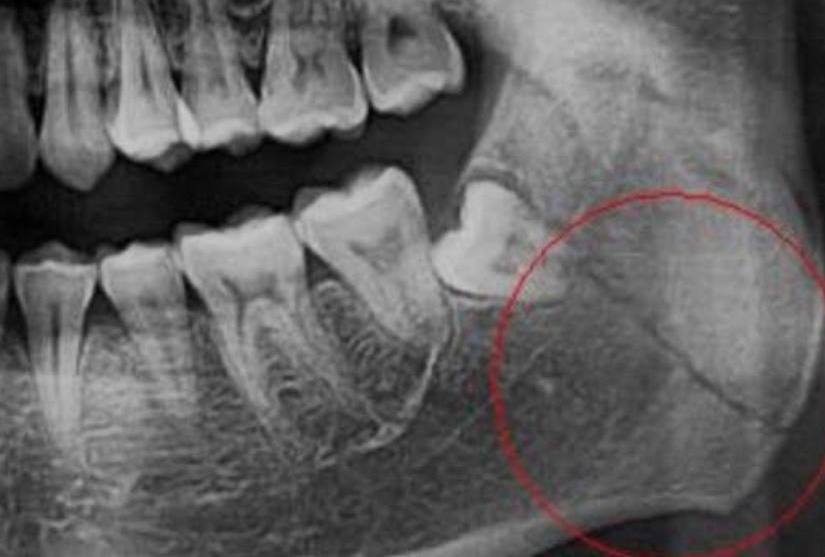

И нам, как стоматологам, в зимнее время часто встречаются травмы зубов и челюстей разной сложности 😣🦷